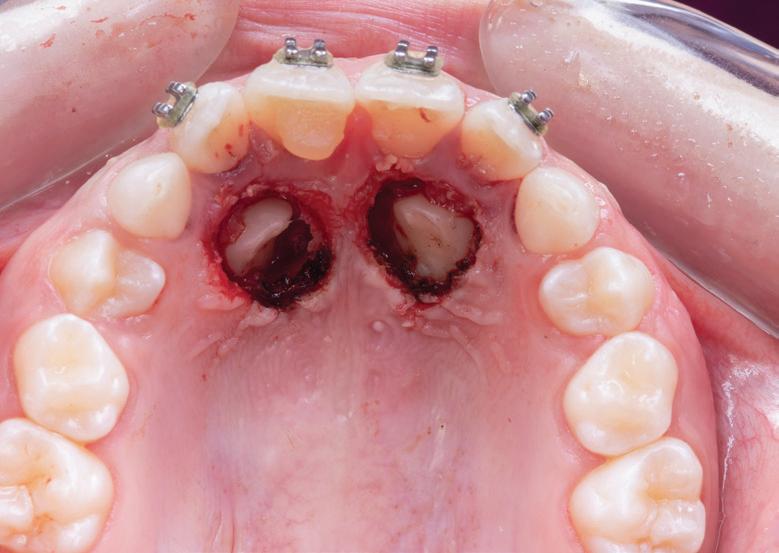

4. Septomatrix pe poziție.

izolarea cu digă de cauciuc, restaurarea din amalgam a fost îndepărtată complet și s-a obținut accesul la cavitatea carioasă (fig. 3-5). În ciuda proximității față de țesutul pulpar, nu a avut loc nicio expunere, iar cavitatea de clasa a II-a a fost restaurată complet cu Biodentine™ (fig. 6-8).

6. Biodentine™ aplicat prin procedura

Bio Bulk-Fill. 7. Situația clinică după 12 minute și îndepărtarea matricii.

8. Situația clinică după îndepărtarea digii de cauciuc. 9. Radiografia de control la 2 luni postoperator.